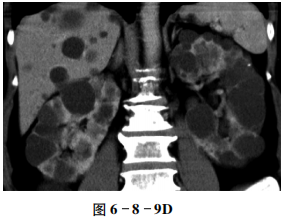

【CT征象】

平扫示双肾,体积增大,边缘不规则,肾内见弥漫性大小不等的囊状低密度区,部分为高密度,部分囊壁见点状钙化,肾皮质变薄(图6-8-9A);增强扫描病变未见明显强化,双侧肾盏、肾盂明显受压(图6-8-9B、C);肝内亦可见多发无强化囊性病变,边缘光滑锐利(图6-8-9D)。

双肾及肝弥漫大小不等囊性病变,边缘光整,无强化。

多囊肾,多囊肝,部分囊壁钙化。

CT表现

①婴儿型:双肾增大,外形保持,肾内布满数毫米大小的囊肿,不伴肾盏、肾盂变形,常合并肝、脾囊肿,少数活到成人者可见门脉高压征象。②成人型:双肾增大,外形呈分叶状,皮髓质内见大小不等的薄壁囊肿,呈蜂窝状,增强扫描囊间肾实质可强化,肾盏、肾盂受压变形,约1/3的病例可合并肝、脾、胰腺囊肿,并常见肾结石。